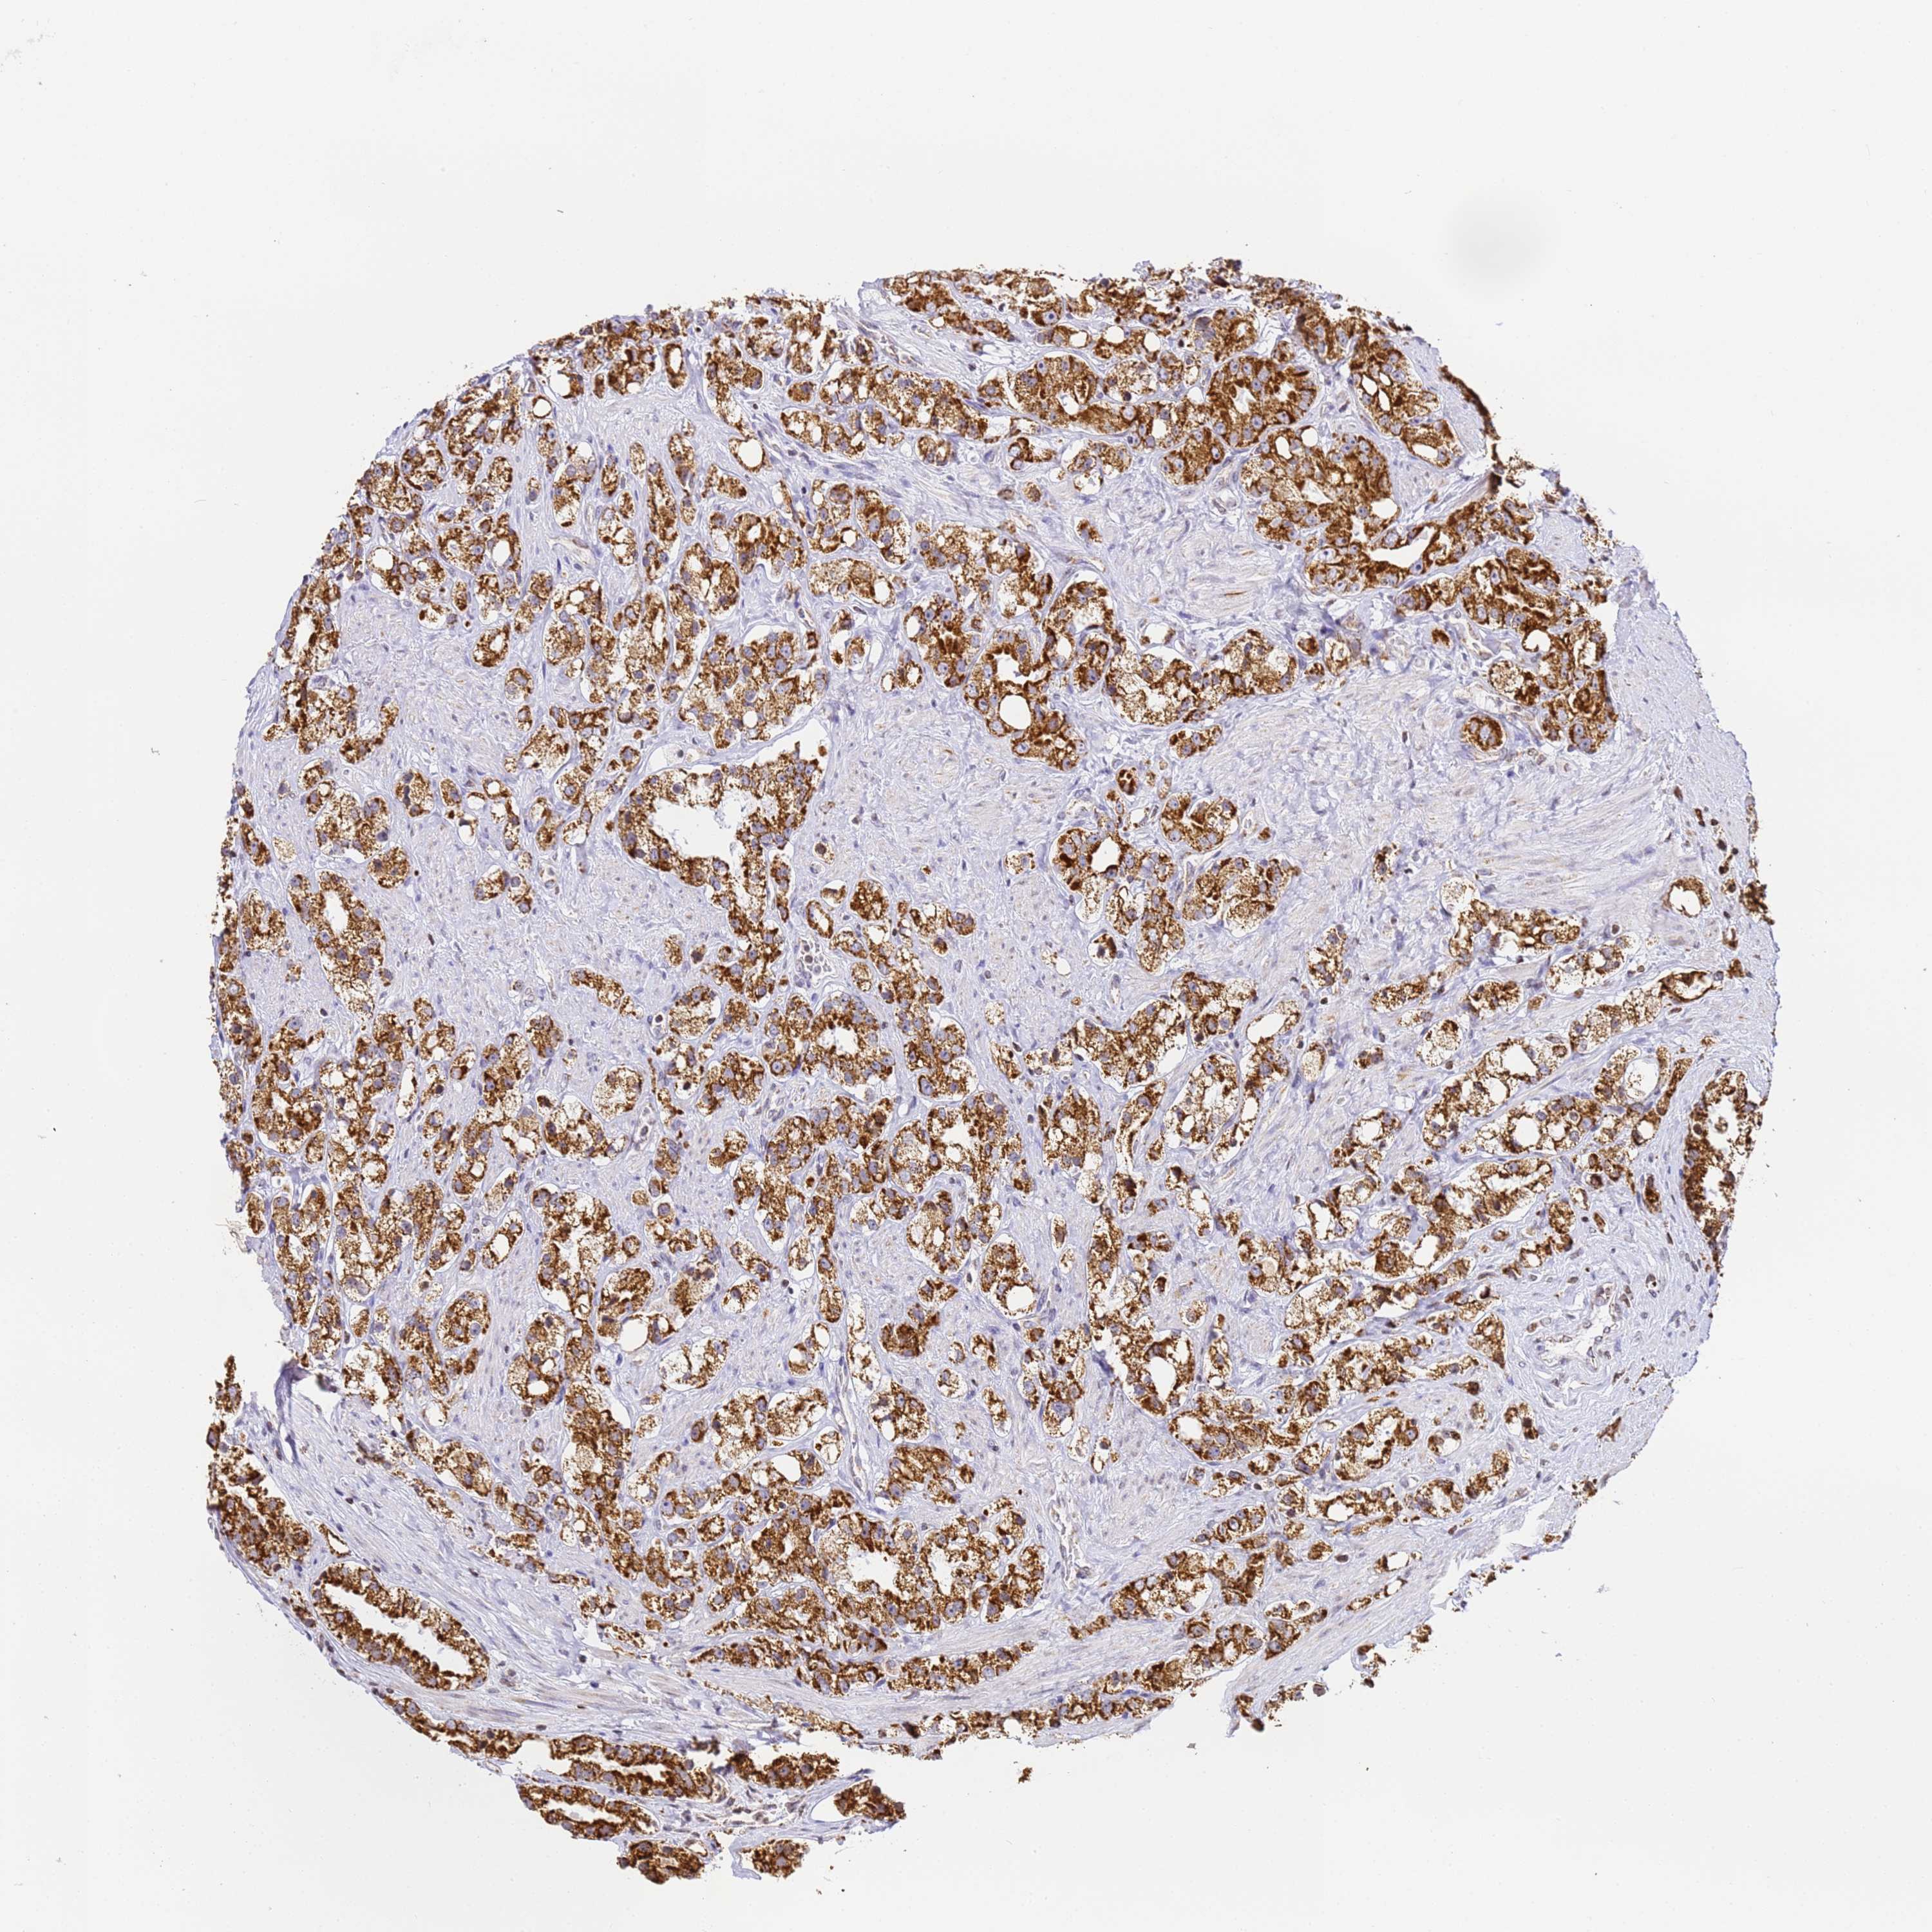

PROSTATE CANCER - Protein expressioni

A mouse-over function shows sample information and annotation data. Click on an image to view it in a full screen mode. Samples can be filtered based on level of antibody staining by selecting one or several of the following categories: high, medium, low and not detected. The assay and annotation is described here.

Note that samples used for immunohistochemistry by the Human Protein Atlas do not correspond to samples in the TCGA dataset.

Antibody stainingi

Antibody staining in the annotated cell types in the current human tissue is reported as not detected, low, medium, or high, based on conventional immunohistochemistry profiling in selected tissues. This score is based on the combination of the staining intensity and fraction of stained cells.

Each image is clickable and will lead to virtual microscopy that enables deeper exploration of all samples and also displays staining intensity scores, fraction scores and subcellular localization as well as patient and tissue information for each sample.

Antibody HPA038755

Antibody HPA048272

Antibody CAB017366

Staining

High

Medium

Low

Not detected

Intensity

Strong

Moderate

Weak

Negative

Quantity

>75%

75%-25%

<25%

None

Location

Nuclear

Cytoplasmic/membranous

Cytoplasmic/membranous,nuclear

Adenocarcinoma, NOS

Adenocarcinoma, High grade

Adenocarcinoma, Low grade